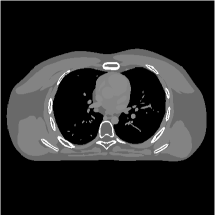

III.C. Low-dose Experiments with Mayo Clinic Data

First, we study transform training based on Mayo Clinic data. As shown in Fig. 6, seven slices obtained at regular dose from three patients are used for transform learning. The number of pixels . Similar to the phantom experiments, overlapping patches are extracted with a patch stride. The number of overall training patches is about . We set for ST, , , for MARS2, , , , , for MARS3, , , , , , , , , for MARS5, , , , , , , , , , , , , for MARS7. The iteration number in Algorithm 1. Fig. 7 illustrates the learned transforms obtained with Mayo Clinic data. Different from the XCAT phantom case, these transforms up to MARS5 display more complex features and structures. The rich features of the MARS models better sparsify the training images over layers compared to the single-layer model (ST).

III.C.2. Simulation Framework, Reconstruction Results, and Comparisons

The synthesized low-dose clinical measurements are simulated from regular-dose images at a resolution of mm with a fan-beam CT geometry corresponding to a monoenergetic source at incident photon intensity . The sinograms are of size . The width of each detector column is mm, the source to detector distance is mm, and the source to rotation center distance is mm. We reconstruct images of size with the pixel size being mm mm.

We conducted experiments on one test slice used for parameter tuning (L067-slice 120) and four independent test slices (L109-slice 90, L192-slice90, L333-slice140, L506-slice 100) of the Mayo Clinic data. For PWLS-EP, we ran iterations using relaxed OS-LALM and set regularization parameter . We used the same as the phantom experiments for Algorithm 2. The process of selecting a general set of reconstruction parameters () for the Mayo Clinic test slices is identical to that for the XCAT phantom in Section III.B.2. The selected regularization parameter and the parameters that control the sparsity of the coefficient maps are for ST, , , , , for MARS2, , , , , , , for MARS3, , , , , , , , , , , for MARS5, and , , , , , , , , , , , , , , for MARS7, respectively.

Figs. 8, 9, 10, and 11 show the reconstructions of the four independent slices using the FBP, PWLS-EP, PWLS-ST, PWLS-MARS2, PWLS-MARS3, PWLS-MARS5, and PWLS-MARS7 schemes, respectively. Additional Mayo Clinic experimental results of the parameter tuning case (Fig. 15) are shown in the supplementary document. Table 1 lists the RMSE and SSIM values of reconstructions of the four independent test slices, with the best values bolded. Generally, the five and seven layer models provided the best RMSE and SSIM values. They outperform the single-layer model by HU in RMSE on average. However, the MARS5 and MARS7 models perform similarly. In order to strengthen the benefits of the multi-layer model, Table 2 lists the RMSE of the reconstructions in four different ROIs (shown in the reference of Fig. 11) with seven methods for slice 100 of patient L506. By observing the reconstructed images, we see that although the ST model achieves a cleaner reconstruction result than FBP and PWLS-EP, it still sacrifices some sharpness of the central region and suffers from loss of details. The deeper models have a somewhat more positive effect in terms of maintaining subtle features, which is clearly more essential to clinical diagnosis. Furthermore, as we will discuss later, after considerable parameter tuning, we found that the information contained in residual maps is gradually decreased with the number of layers, eventually vanishing at some layer, which suggests that very deep unsupervised models might not offer significantly better image quality.